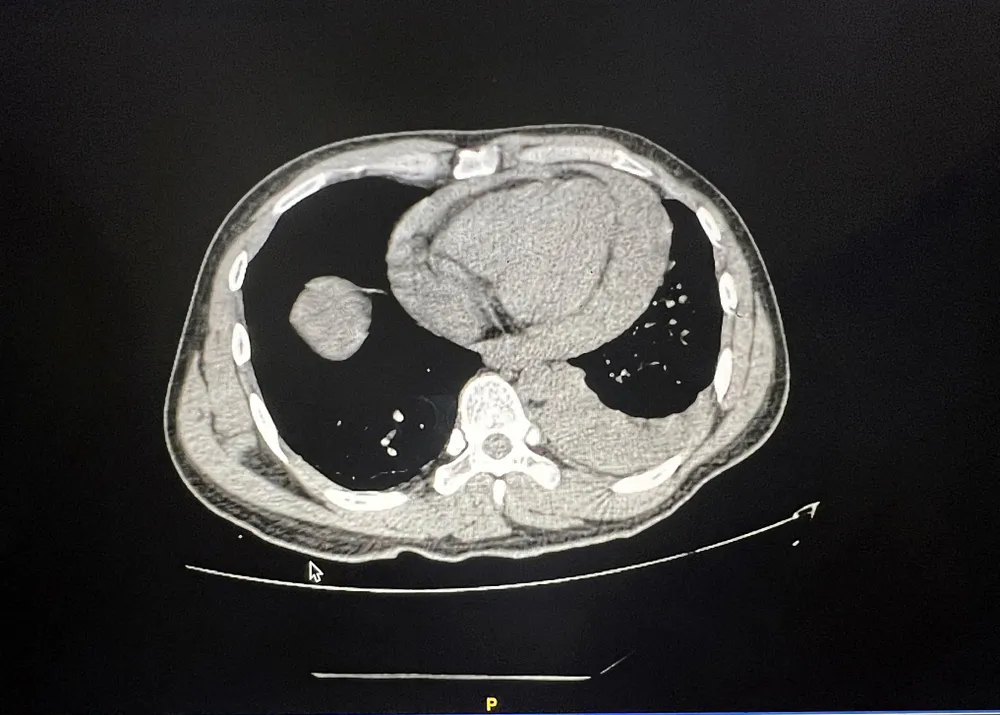

Chụp CT ngực, các bác sĩ (BS) phát hiện bệnh nhân bị tràn máu màng tim, màng phổi trái nên nghĩ ngay đến vết thương thấu tim.

17 giờ cùng ngày, bệnh nhân được đưa vào phòng mổ. Tình trạng bệnh nhân khi lên bàn mổ vô cùng nguy kịch khi bị choáng do vết thương thấu ngực trái, thủng tâm thất phải đến 1,5 cm, thủng thuỳ giữa phổi phải gây tràn máu màng tim, màng phổi trái… Bệnh nhân được truyền 4 đơn vị máu trong quá trình phẫu thuật.